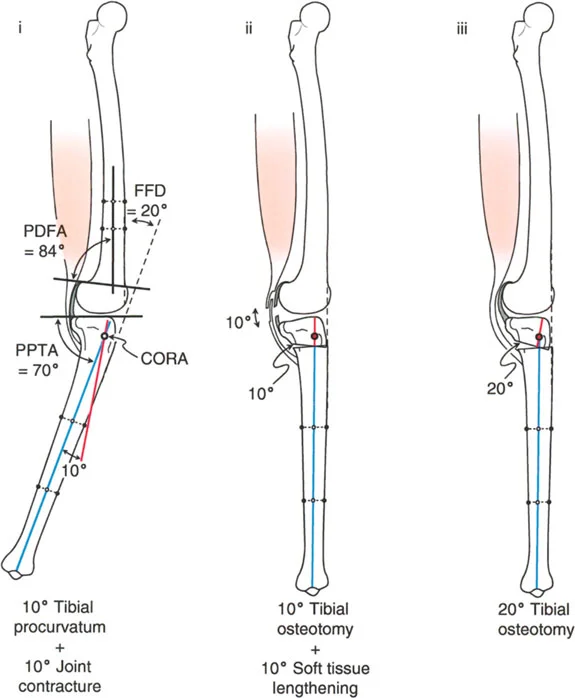

تصحيح تحدد حركة الركبة (Flexion Deformity - FFD)

تحدُّد حركة الركبة هو عدم القدرة على مد الركبة بالكامل. يمكن أن يكون سببه عظميًا أو ناتجًا عن تقلص في الأنسجة الرخوة.

- التشخيص الدقيق: يجب تحديد ما إذا كان تحدد الحركة ناتجًا عن تشوه عظمي (تقوس أمامي في الفخذ أو الساق) أو تقلص في الأنسجة الرخوة (الأوتار الخلفية، محفظة المفصل).

- قطع العظم التمديدي (Extension Osteotomy):

- إذا كان التشوه عظميًا، يتم إجراء قطع عظم تمديدي في عظم الفخذ أو الساق لتصحيح التقوس.

- الأستاذ الدكتور محمد هطيف يؤكد على أهمية عدم تصحيح الساق بأكثر من 90 درجة PPTA لتجنب فقدان الميل الخلفي الطبيعي للساق.

- تحرير الأنسجة الرخوة (Soft Tissue Release):

- إذا كان السبب هو تقلص الأنسجة الرخوة، فقد يتم إجراء إطالة للأوتار أو تحرير لمحفظة المفصل.

تصحيح الركبة الارتدادية (Recurvatum Deformity - Hyperextension)

الركبة الارتدادية هي فرط البسط في الركبة. غالبًا ما تكون غير مصحوبة بأعراض في الأشخاص ذوي العضلات السليمة، ولكنها قد تسبب مشاكل في حالات ضعف العضلات أو التشوهات العظمية.

- التشخيص: يجب تحديد ما إذا كانت الارتدادية عظمية (تقوس خلفي في الفخذ أو الساق) أو ناتجة عن رخاوة في الأنسجة الرخوة أو ضعف عضلي.

- قطع العظم الانثنائي (Flexion Osteotomy):

- إذا كان التشوه عظميًا (تقوس خلفي)، يتم إجراء قطع عظم انثنائي في عظم الفخذ أو الساق لتصحيح الارتدادية.

- الأستاذ الدكتور محمد هطيف يشدد على أهمية عدم استخدام قطع عظم الفخذ الانثنائي لتصحيح ارتدادية الساق، والعكس صحيح، لتجنب الانزلاق الخلفي أو الأمامي للركبة.

- اعتبارات خاصة: في المرضى الذين يعانون من ضعف عضلي (مثل شلل الأطفال)، قد يحتاج التصحيح إلى فرط تصحيح بسيط (overcorrection) إلى وضعية انثناء لضمان ثبات الركبة ومنع فرط البسط غير المتحكم فيه.